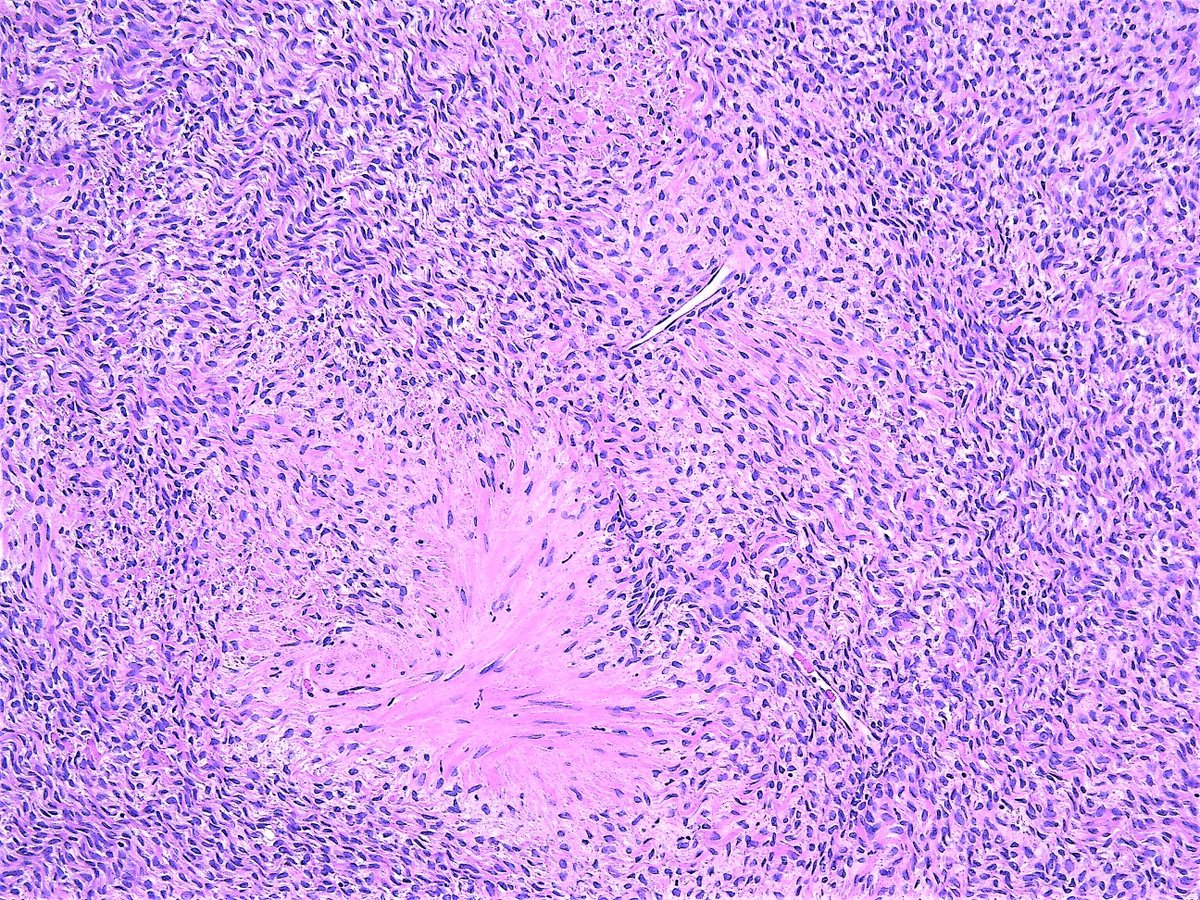

Thecoma. Ovary, resection.

#Pathology#Pathologist#Gynpathpic.twitter.com/tHEJ0T3EiG